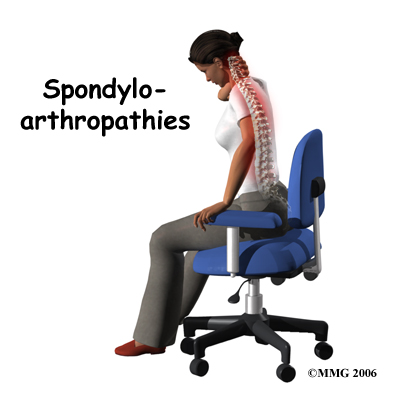

Welcome to Ari Levine PT, PC's resource about Spondyloarthropathies.

There are many different types of rheumatological diseases that affect the spine. A rheumatological disease is a problem that affects the entire body as a whole, rather than just one joint, such as the relatively well-known rheumatoid arthritis. When a rheumatological disease affects the spine, the resulting conditon is called a spondyloarthropathy. The term is made up of the Greek words: "Spondylo" meaning "vertebra," "arthro" meaning "joint," and "pathos" meaning "disease."

This group of diseases cause damage by creating inflammation that attacks the connective tissues of the body. Connective tissue makes up many structures in the body including bones, tendons, ligaments, cartilage, blood and lymphatic tissue. In most cases, the cause of these diseases is unknown. There is increasing evidence that the underlying cause may be a combination of genetics and infection. A person born with certain genes may react differently to certain types of infections. Once that person is exposed to certain infections, the body responds by defending itself. The way the body defends itself against infection is through an inflammatory response. This is normal. What is not normal is that long after the infection is gone, the inflammation continues. This chronic inflammation causes damage to many of the connective tissue structures in the body often causing pain and dysfunction.